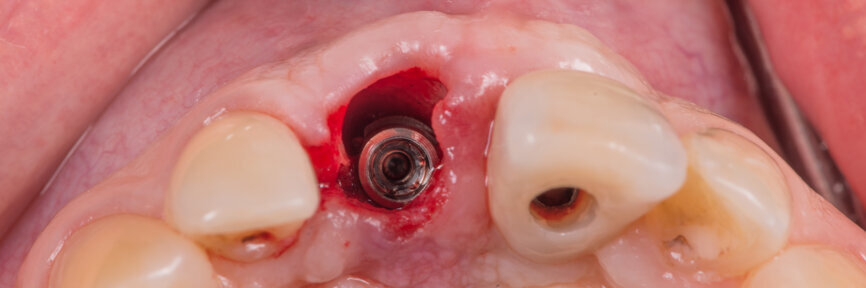

Tooth #11 was extracted atraumatically without raising a flap or performing an osteotomy (Fig. 4). The extraction socket was meticulously cleaned and rinsed with Betadine. The drilling sequence included 2.2, 2.8, 3.2 and 3.7 mm drills (Fig.5). The implant was placed with a final torque of 80 N cm (Figs. 6 & 7). In its final position, the implant platform lay 4 mm below the ideal gingival margin (at the same level of the adjacent implant platform; Fig.8).

A Regular Base (RB) titanium temporary abutment for a crown was placed and a laboratory-made shell was positioned without interference with the temporary abutment (Fig. 9). The surgical site was protected with a small piece of rubber dam (Fig. 10), and the abutment was connected to the shell with a dual-curing luting composite (Fig. 11). The development of a proper emergence profile will be done extra-orally (Fig. 12) to produce the screw-retained temporary crown.

Before placing the provisional crown, the gap between the implant and the buccal plate was filled with a particulate xenograft material (cerabone, botiss biomaterials). The graft was packed up to the gingival margin according to the dual-zone principle described by Chu et al. (Fig. 13).[7] The screw-retained temporary crown was then torqued to 35 N cm (Fig. 14).